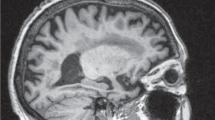

An early intervention of Alzheimer’s disease (AD) is highly essential due to the fact that this neuro degenerative disease generates major life-threatening issues, especially memory loss among patients in society. Moreover, categorizing NC (Normal Control), MCI (Mild Cognitive Impairment) and AD early in course allows the patients to experience benefits from new treatments. Therefore, it is important to construct a reliable classification technique to discriminate the patients with or without AD from the bio medical imaging modality. Hence, we developed a novel FCM based Weighted Probabilistic Neural Network (FWPNN) classification algorithm and analyzed the brain images related to structural MRI modality for better discrimination of class labels. Initially our proposed framework begins with brain image normalization stage. In this stage, ROI regions related to Hippo-Campus (HC) and Posterior Cingulate Cortex (PCC) from the brain images are extracted using Automated Anatomical Labeling (AAL) method. Subsequently, nineteen highly relevant AD related features are selected through Multiple-criterion feature selection method. At last, our novel FWPNN classification algorithm is imposed to remove suspicious samples from the training data with an end goal to enhance the classification performance. This newly developed classification algorithm combines both the goodness of supervised and unsupervised learning techniques. The experimental validation is carried out with the ADNI subset and then to the Bordex-3 city dataset. Our proposed classification approach achieves an accuracy of about 98.63%, 95.4%, 96.4% in terms of classification with AD vs NC, MCI vs NC and AD vs MCI. The experimental results suggest that the removal of noisy samples from the training data can enhance the decision generation process of the expert systems.